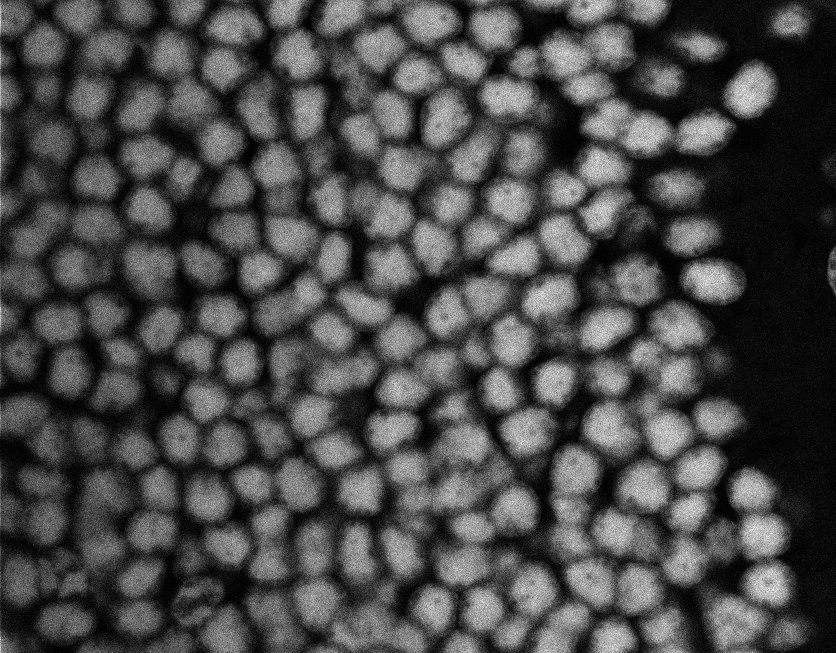

Nuclei